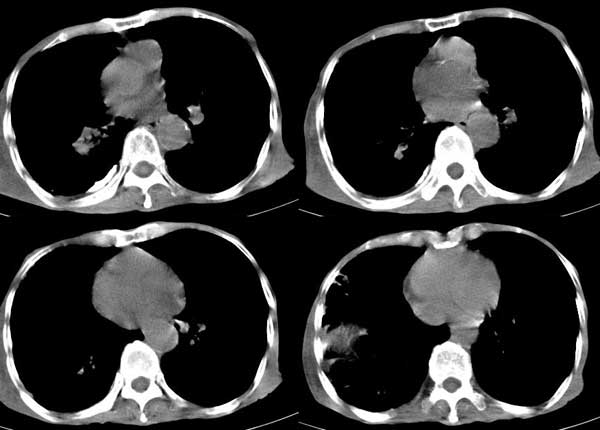

患者男,81岁,咳喘10余年,继往结核病史,发现胸部体表肿物(具体时间不详)就诊

右侧胸廓塌陷。右前上外侧胸壁软组织肿块,其内见有低密度影,肋骨呈溶骨性表现。右肺上叶见大量的间质纤维化表现。右侧膈肌上抬。

患者男,81岁,咳喘10余年,继往结核病史,发现胸部体表肿物

考虑:1、继发性结核,右结核性胸膜炎伴胸壁结核性感染

2、右侧胸壁恶性肿瘤。

肺尖巨大肿块影阴,胸壁受侵肋骨破坏,肿块密度不均且穿破胸壁入皮下,应该是:肺上沟癌;由于肺内有斑片状播散病灶,因此不排除胸壁结核。

我觉得这个人右侧胸部的肿块来源于肋骨或胸壁软组织,从病灶的形态来和最大直径来看,来源于肋骨的可能更大,可以基本定性为恶性。

患者男,81岁,咳喘10余年,继往结核病史,发现胸部体表肿物。

考虑:1 右侧胸壁恶性肿瘤(多考虑:胸膜间皮瘤)。

2 继发性结核,右结核性胸膜炎伴胸壁结核性感染。